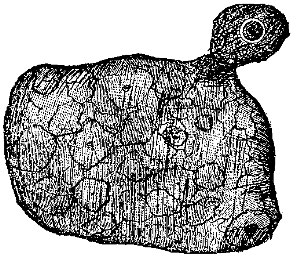

The Male Elements.—The spermatozoa are exceedingly delicate and minute; they constitute the greatest part of the semen, or sperm. They are peculiar shaped bodies, having a head, body, and tail, as illustrated in the accompanying figure, and they can only be seen by powerful magnifying glasses. (Fig. 1.)

[Pg 7]The Female Element.—As I have already said, the female germ-cell is also known as the ovum, or egg. A single ovum is shown in Fig. 1.

| Fig. 8. This figure illustrates the course followed by an ovum. The ripened egg leaves the ovary (1), passes down the Fallopian tube (2), and thence into the uterine cavity (3). | Fig. 9. An exceedingly minute piece of an ovary, highly magnified. It shows eight ova or eggs. |

Object of Ovaries.—The ovaries are the essential organs of generation in the female. In each ovary are large numbers of cells, ovules, or eggs, one of which, at least, is supposed to pass into the uterine cavity with each menstruation. Anatomists tell us that each human ovary contains as many as 30,000 of these ovules, or eggs.